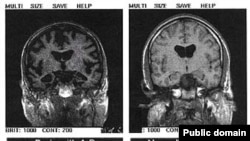

Мозг человека, пораженный синдромом Альцгеймера